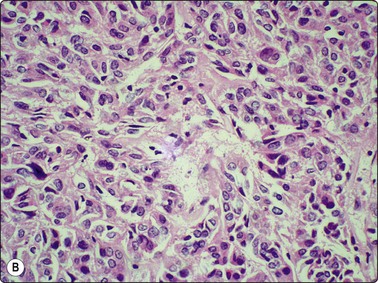

Until recently, thyroid carcinoma with a poorly differentiated insular pattern was considered to be a distinct entity, a thyroglobulin-producing neoplasm, intermediate in aggressiveness between well-differentiated and anaplastic thyroid carcinoma. Reports have appeared documenting cytological features in insular carcinomas such as high cellularity, dispersed and loosely aggregated cells, solid, cohesive trabecular or papillaroid structures, intact insulae, fragile, ill-defined, granular cytoplasm, oval, hyperchromatic nuclei, occasional INCIs and/or grooves.151-155 However, as insular pattern is often admixed with trabecular and solid growth patterns, the more suitable term ‘primordial carcinoma’ was suggested for this entity.156

The current concept of pure poorly differentiated thyroid carcinoma, as per the Turin proposal156 is one that shows a histologically mixed solid/trabecular/insular architecture, absence of conventional nuclear features of PC and the presence of one of the following three features: cells with convoluted (raisin-like) nuclei, a mitotic index of ≥3 mitoses/10 high-power fields and tumor necrosis. Most tumors are immunohistochemically positive for thyroglobulin and thyroid transcription factor 1, and a subset is also positive for p53.157 Ras mutations are common.

Smears in poorly differentiated thyroid carcinomas are hypercellular with single cells as well as cells in solid, trabecular and insular patterns. There is marked crowding of cells and tumor cells show high nuclear cytoplasmic ratios (Fig. 6.28).158

image image image

Fig. 6.28 Poorly differentiated carcinoma

(A,B) Smears showing syncytial clusters of crowded small cells with hyperchromatic nuclei (A, MGG, HP; B, Pap, HP); (C) Tissue section, same case. (H&E, IP).